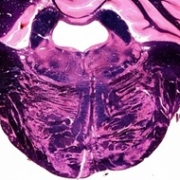

Tracts and Nuclei

Please click one of the following photos to enter the respective section.